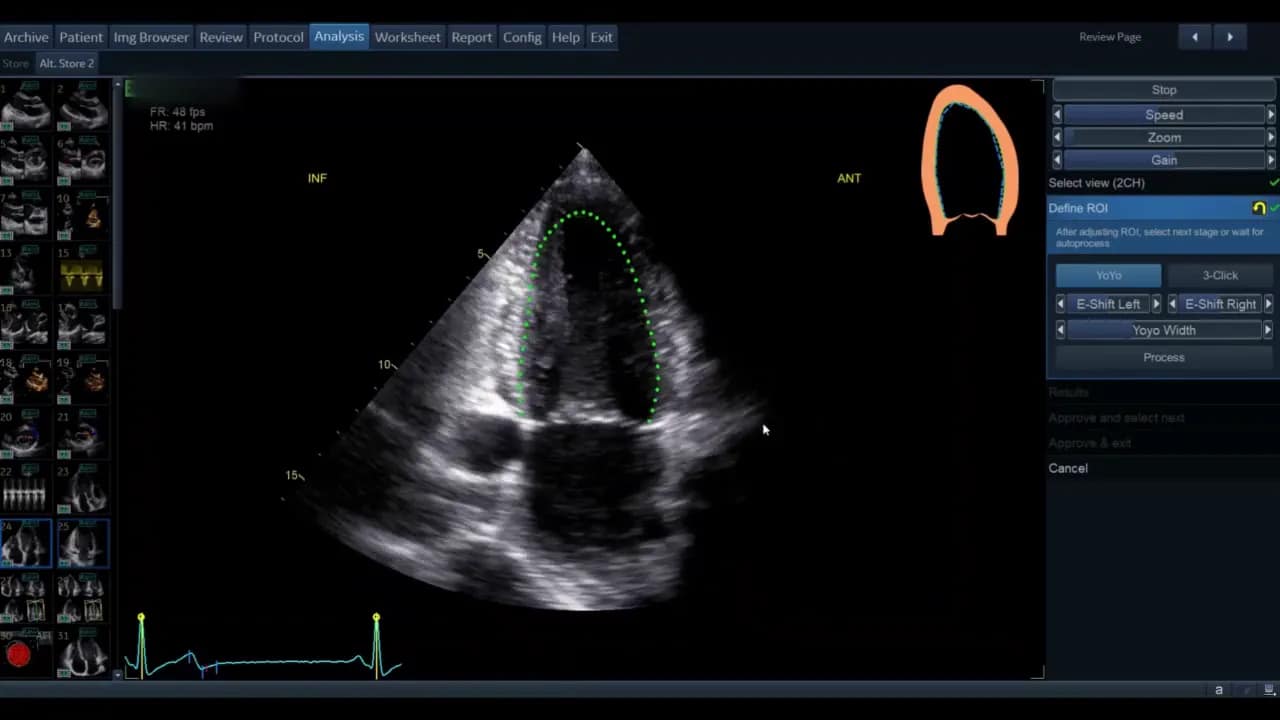

Sobald die Ansicht gewählt ist, gelangen Sie in die Phase der ROI‑Definition. Hier legt die Software die initiale Kontur für die automatische Wandsegmentverfolgung fest.

Die Standardkontur wird als grüne Linie (modellabhängig) angezeigt. Bewegen Sie den Cursor über diese Linie; rote Kreise erscheinen als Griffpunkte, die Sie anklicken, verschieben und loslassen können. Ziel ist eine möglichst genaue Platzierung entlang des inneren Myokardrandes ohne Papillarmuskeln und Trabekel zu ignorieren, soweit die Software dies zulässt.

- Wenn die vorgegebene Kontur passend ist, genügt das geringe Feintuning.

- Wenn die Kontur unbrauchbar erscheint, nutzen Sie die Drei‑Punkt‑Option. Dabei markieren Sie basal‑septal, basal‑lateral und den Apex manuell. Die Software interpoliert zwischen den Punkten.

Nach der manuellen Markierung können Sie die so erzeugte grüne Kontur wiederum per Griffpunkte feinjustieren. Ziel ist, dass die Kontur den endokardialen Rand im gesamten Zyklus plausibel abdeckt.

Klicken Sie auf Process, um die automatische Verfolgung starten zu lassen. Die Software identifiziert dann den Enddiastolen‑ und Endsystolen‑Frame.